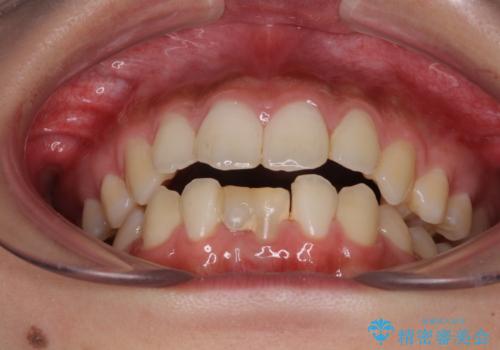

- 下顎前歯に乳歯が残っており、欠損もしていることを気にして来院された患者様です。

舌の突出癖が顕著にあり、上下前歯が非接触となっており、上顎前歯が前方に突出している状態でした。